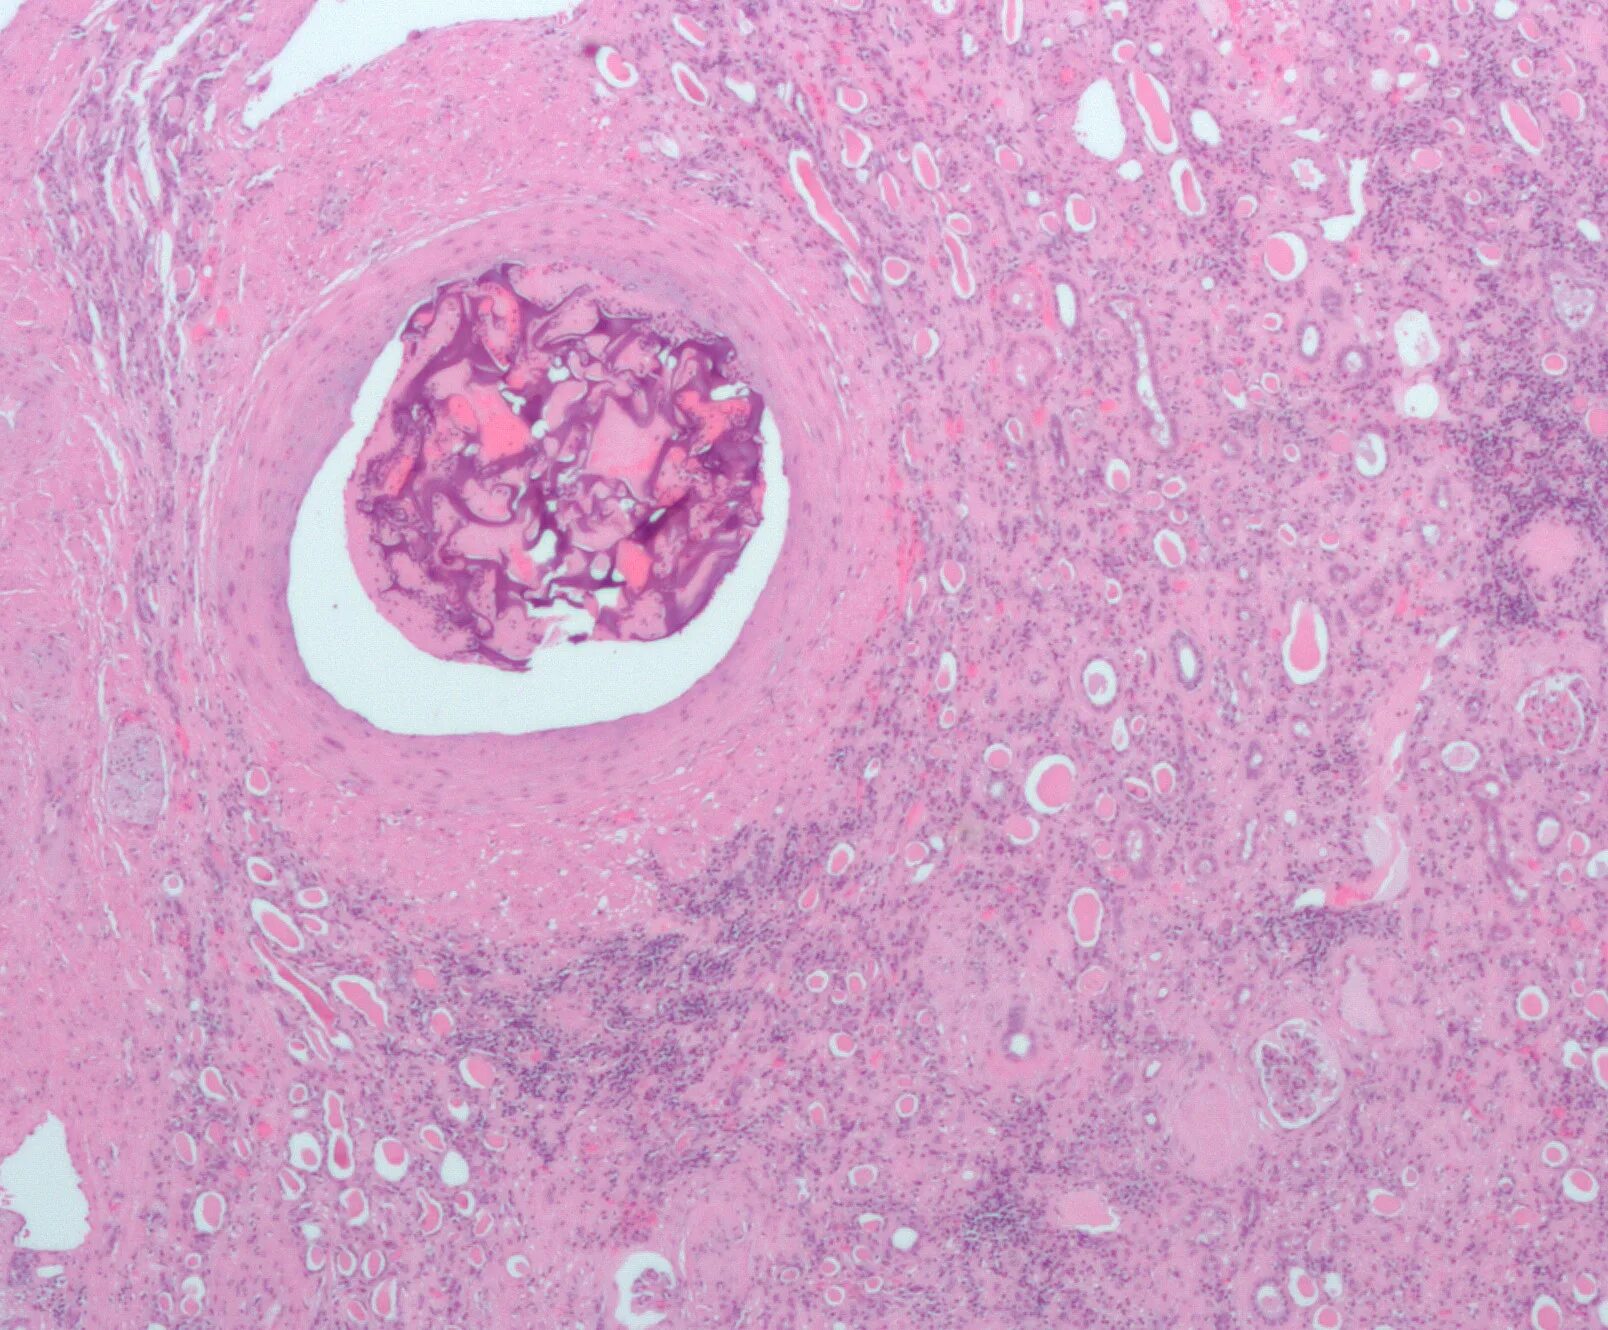

Фиброзно хрящевая эмболия у собак